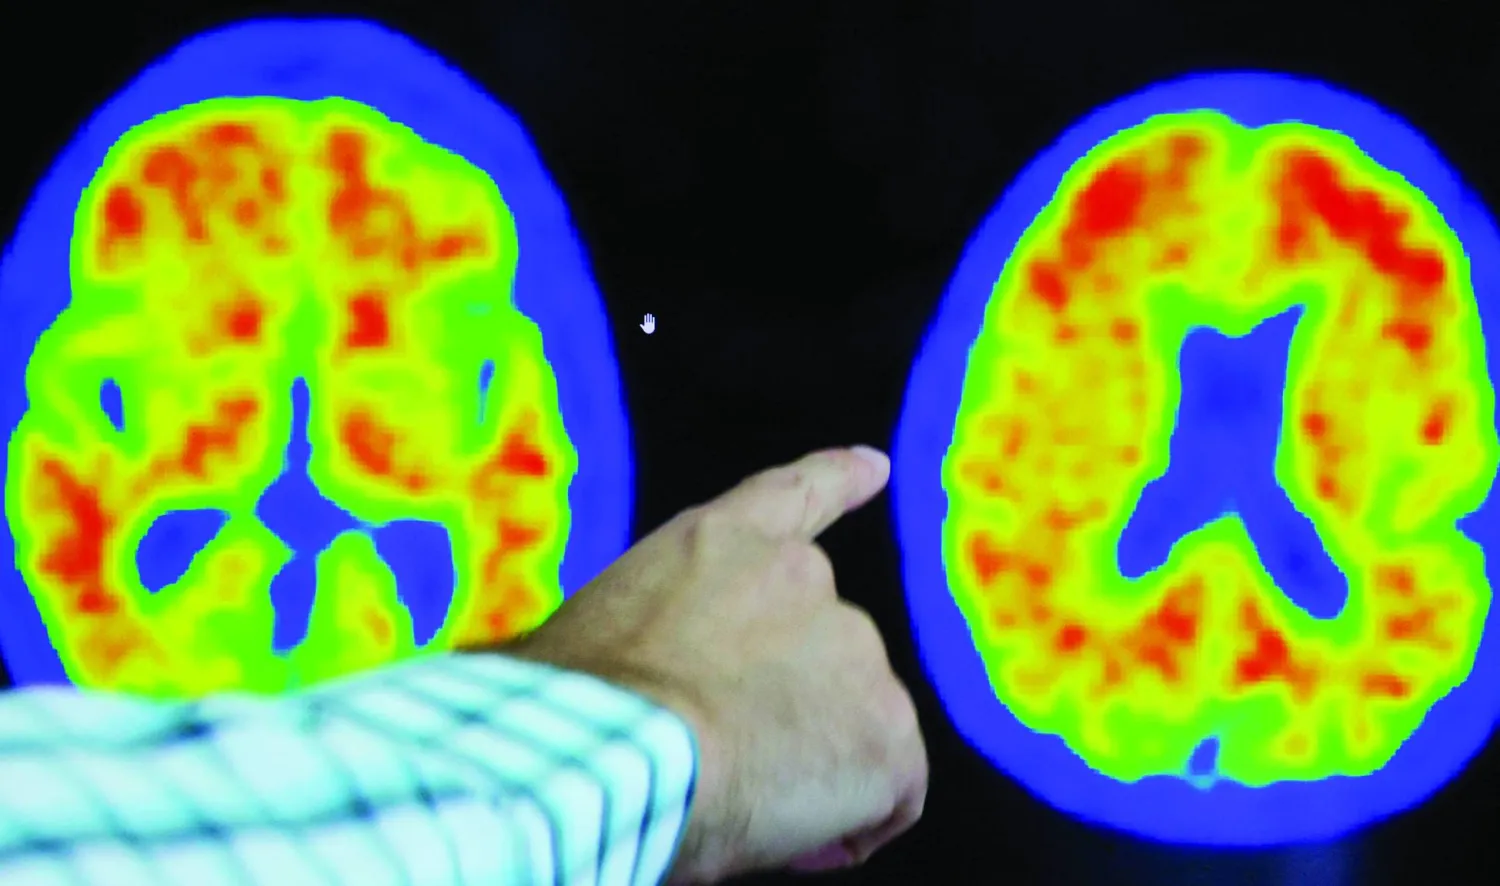

توصلت دراسة جديدة إلى أن تعزيز بروتين واحد في الدماغ يمكن أن يعيد تنشيط خلايا المخ المُتقدمة في السن؛ الأمر الذي قد يلعب دوراً رئيسياً في التصدي لمرض ألزهايمر.

وفي اختبارات السلوك والذاكرة، كان أداء الفئران التي تمتلك مستويات أعلى من Sox9 أفضل، مما يشير إلى أن تعزيز هذا البروتين يمكن أن يساعد في حماية الدماغ وعكس التدهور المعرفي - وهي عملية تحدث عادة في مرض ألزهايمر حيث تتلف الخلايا العصبية وتُدمَّر.

ومرض ألزهايمر هو مرض عصبي تنكسي يؤدي إلى التدهور التدريجي للوظائف المعرفية، مثل الذاكرة، واللغة، والتفكير، والسلوك، والقدرات على حل المشكلات. وهو السبب الأكثر شيوعاً للخرف؛ حيث يمثل 60 - 80 في المائة من الحالات.